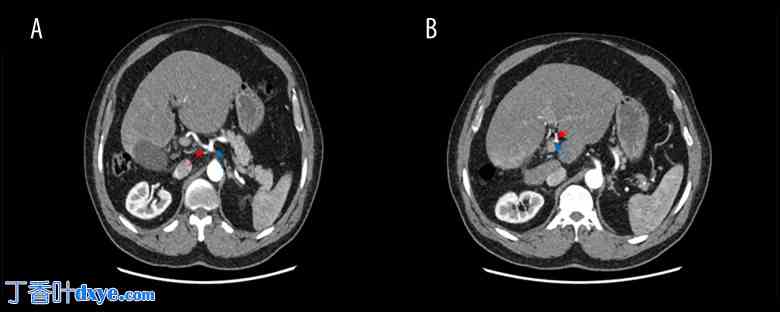

患者被诊断为急性胆囊炎,入院并安排接受腹腔镜胆囊切除术。术中,患者被置于常规推荐的反头低脚高体位,略向左倾斜。所有端口均按常规方式插入:1 个位于脐上,1 个位于上腹部,2 个位于右上腹。胆囊严重炎症坏死,出现坏疽性胆囊炎征象,胆囊与大网膜和小肠粘连;胆囊右叶未见显影,胆囊位于 IV 段侧床(图 4)。腹腔镜粘连松解术采用锐器和钝器分离,借助能量装置,方便在腹腔镜下完成手术,避免中转开腹手术。术中,由于粘连紧密,解剖识别颇具挑战性。因此,采用逆向底面入路,向下解剖至Calot三角水平,以安全地识别胆道结构。清晰勾画出解剖结构后,识别、夹闭并解剖胆囊管和胆囊动脉。小心地将胆囊从肝床刮除并切除。标本送去进行组织病理学检查。术中及术后均保持止血。无术中及术后并发症。患者次日恢复良好,出院回家。一周后患者来院复诊,恢复良好,除切口处轻微疼痛外,无其他不适。随访实验室检查结果正常。

图4

腹腔镜视图 (A, B)。肝右叶发育不全,胆囊位置明显错位,位于背侧。